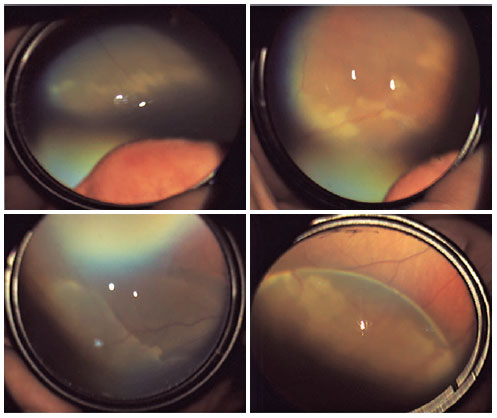

Of the 2972 neonates who underwent ophthalmological examination, 185 (6.2%) presented with abnormal findings. Retinal hemorrhages were the most common finding among these, observed in 2.3% (n=68) of all screened neonates, and they were bilateral in 55.8% (n=8) of the neonates. Moreover, 61.7% (n=42) of all hemorrhages included the midperipheric and peripheric retina, whereas 38.2% (n=26) included the macula and peripheral retina together. At the 3-month follow-up, all retinal hemorrhages had resolved spontaneously. Retinal hemorrhages were also more frequent in the vaginal deliveries (n=60) in the present study. Figure 1 depicts retinal hemorrhages detected in neonates during the ophthalmological examination.

The second-most common finding was white changes in the retina, which was recorded in 1.9% (n=55) of all screened neonates (Figure 2). Cases of retinal white changes in various forms, such as a spot, strip, or patch, were also recorded.